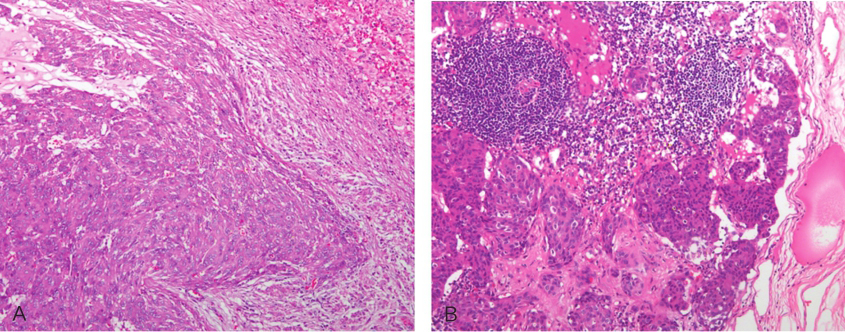

术后病理:(胃GIST伊马替尼治疗后)①(远端胃及部分肝脏)胃肠间质瘤(胃肿瘤大小:14cm×4cm;肝脏肿瘤大小:0.8cm×0.5cm及1.3cm×1.1cm;核分裂象:10个/50HPF)(图4);胃体断端及幽门断端、肝脏手术切缘未见肿瘤累及。②肝总动脉旁淋巴结(3/7)、小弯侧淋巴结(6/22)、大弯侧淋巴结(2/18)肿瘤转移。③(左侧)卵巢滤泡囊肿(图5、图6)。

图5原发肿瘤HE染色

引自:胃肠间质瘤典型病例诊治与解析.第1版.ISBN:978-7-117-30146-6.主编:陶凯雄 曹 晖

图6肝脏及淋巴结转移灶HE染色

A.肝脏(100×);B.淋巴结(100×)